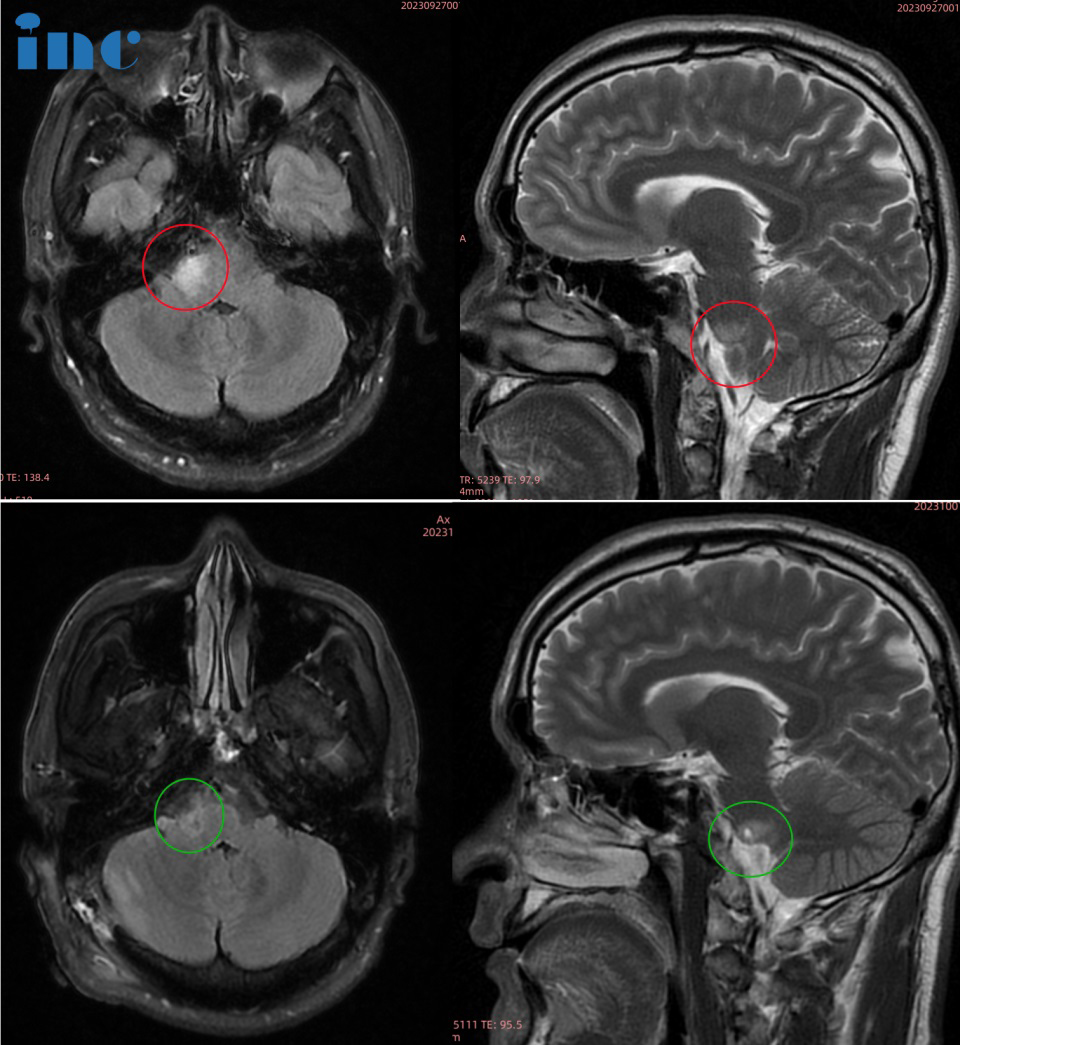

24岁男性-脑干延髓低级别胶质瘤

◉手术日期:2023年6月巴教授疑难示范手术期间

◉患者情况:24岁的川川于2019年中出现无明显诱因的左侧上肢无力,随后伴有头晕头痛症状。进行头颅核磁检查提示:延髓后方结节性病灶。医生建议随诊复查,未做不同治疗。随后症状自行缓解。2023年以来,出现了左侧下肢无力,大约两周后自行缓解。随后出现一过性拖地行走,双眼视力下降,偶有复视。近半年,患者偶有呼吸频率改变,一过性呼气吸气变浅,舌尖麻木。4月份后,患者自感左脚及双侧脸颊麻木、舌尖麻木。2023年5月17日,患者复查MRI提示较前(2020-01-19)轻度增大,倾向良性肿瘤。

◉治疗过程:巴特朗菲教授带领国内神经外科手术团队经过紧张奋战,尽较大的努力切除肿瘤,完全保护延髓神经血管,无任何新发神经功能损伤。

◉术后情况:术后当天ICU巴教授查房,意识清醒、状态良好,对答如流,可以咳嗽、吞咽功能都正常。术后一天顺利转出ICU转入普通病房。川川对巴教授说:"So hungry!"并询问巴教授是否有饮食禁忌。巴教授表示:什么都可以吃,只要你想。术后二天查房:已经下床四处走走。目前川川状态良好,已经逐渐恢复了正常的工作和学习。